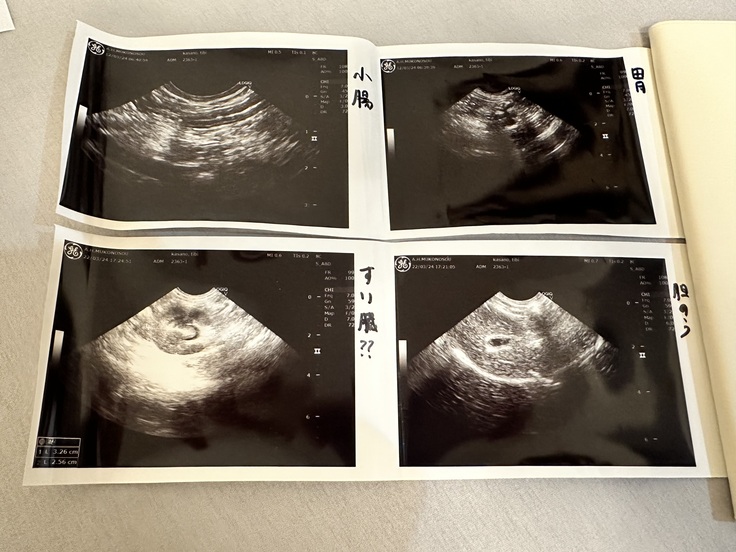

更に膵臓の炎症が広がり、三臓器炎(膵炎、胆のう炎、炎症性腸疾患)が併発していることがわかりました。

(↑膵臓と思われる場所の炎症と胆のうの炎症がわかるエコー)